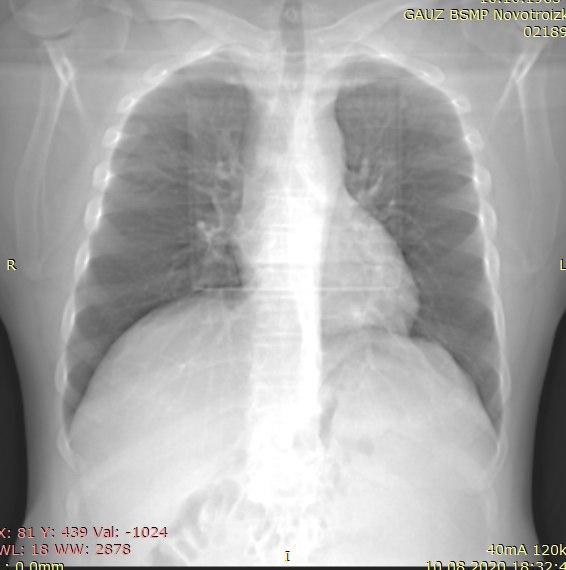

Лев ножки- подозреваем остр инфаркт

Правой- это перегрузка прав отделов, лег гипертензия, тэла

И опять же, блокада остро возникшая или с детства- тоже разные вещи

Правой.